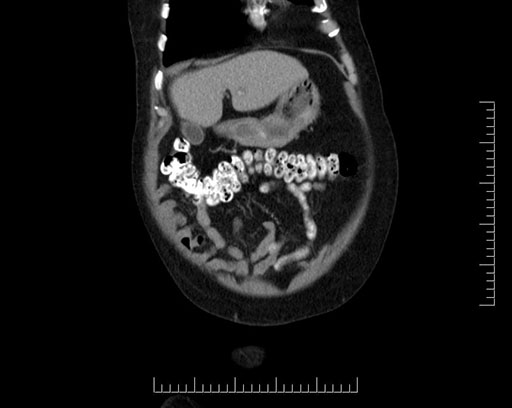

Imaging Analysis

Look through the patient's CT scan to identify any areas of concern for the necessary procedure.

Based on your CT findings, which issue(s) would give reason for "planned slowing down moment(s)" in this case?

Considering a standard Whipple procedure, what step(s) of the operation would you do differently in this case?